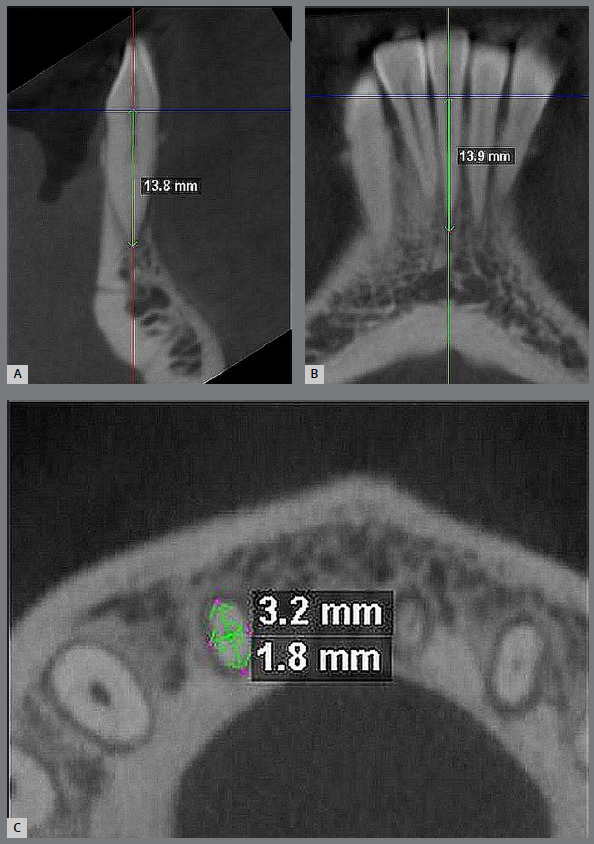

Methods: In this two-arm parallel single-blind randomized controlled trial, forty-four patients with Class I malocclusion with mandibular anterior crowding were recruited form orthodontic clinic of All India Institute of Medical Sciences (Jodhpur, India). Patients were randomly allocated into NiTi and CuNiTi groups, with a 1:1 allocation. Alignment was performed using 0.014-in, 0.016-in, 0.018-in, 0.019x0.025-in archwire sequence in the respective groups, which terminated in 0.019 x 0.025-in stainless-steel working archwire. The primary outcome was alignment efficiency, measured on study models from baseline (T0) to the first, second, third, fourth and fifth-month (T5). Secondary outcome was root resorption, measured from CBCT scans taken at T0 and T5. Mixed-factorial ANOVA was used to compare Little's Irregularity Index (LII). For assessing the proportion of patients with complete alignment at the end of each month, Kaplan-Meier survival curve was built and time to treatment completion was compared between groups using log rank test. Paired t-test was used to assess external apical root resorption (EARR) within groups, whereas independent t-test was used to evaluate LII and EARR between the groups.

Results: Twenty-two patients were recruited in each group. One patient was lost to follow-up in the CuNiTi group. No statistically significant differences were observed in alignment efficiency between the groups (p>0.05). Intergroup comparison revealed that the changes in root measurement in three-dimensions were not statistically significant (p>0.05), except for mandibular right central incisor, which showed increased resorption at root apex in NiTi group (p<0.01).

Conclusion: The two alignment archwires showed similar rate of alignment at all time points. Root resorption measurement did not differ between the NiTi and CuNiTi groups, except for the mandibular right central incisor, which showed more resorption in NiTi group.